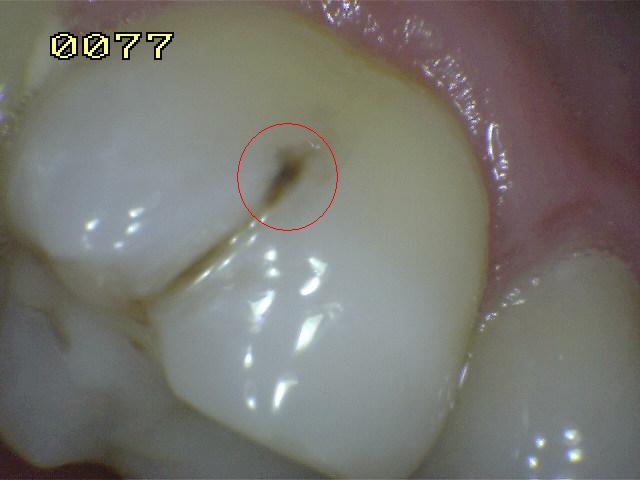

Sistema Internacional para la Detección y Evaluación de Caries (ICDAS)

¿Determine los códigos pertinentes a cada imagen?

Click en el hipervínculo: Para comparar el resultado de su diagnóstico